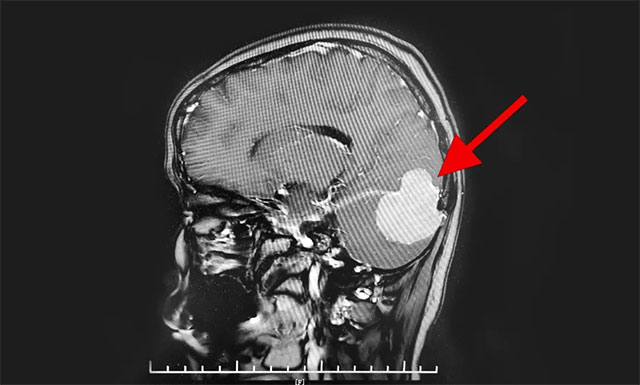

頭顱MR增強(qiáng)顯示,患者右側(cè)后顱窩可見團(tuán)塊狀異常信號病灶,大小近5公分,邊緣清晰,輪廓不規(guī)整,向上凸入枕部,毗鄰右側(cè)小腦半球及枕葉受推壓(右側(cè)小腦少許水腫),右側(cè)橫竇明顯受壓,右側(cè)枕骨受壓變扁。

由神經(jīng)外科6B病區(qū)主任潘仁龍、李士其教授、吳治群博士組成的專家組會診后指出,患者顱內(nèi)占位明確,根據(jù)影像學(xué)表現(xiàn)考慮為小腦幕腦膜瘤,并且腫瘤橫跨小腦幕幕上幕下,十分罕見。腫瘤瘤體向上下兩方向發(fā)展,大部位于后顱窩,瘤體已較大,不及時手術(shù),會出現(xiàn)慢性枕骨大孔疝的急性發(fā)作,導(dǎo)致生命危險,患者手術(shù)指征明確。

▲ 腦膜瘤橫跨小腦幕幕上幕下,十分罕見